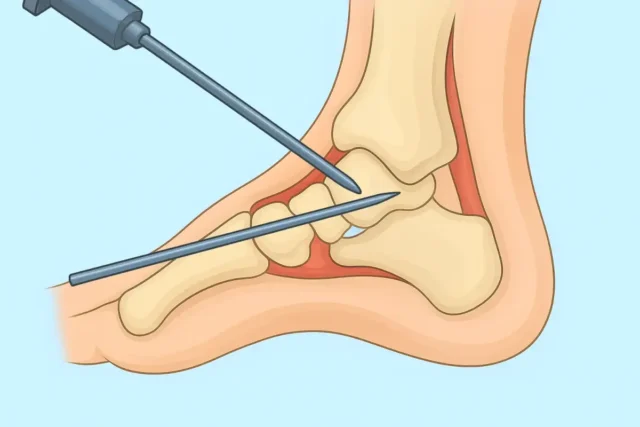

Ayak Bileği Artroskopisi Nedir?

Artroskopi, eklem içi görüntüleme ve tedavi yöntemlerinden biridir. Ayak bileği artroskopisi, ayak bileğinin içerisine yerleştirilen artroskop ile sorunların detaylı bir şekilde incelenmesi ve tedavi edilmesi anlamına gelir. Bu işlem sırasında